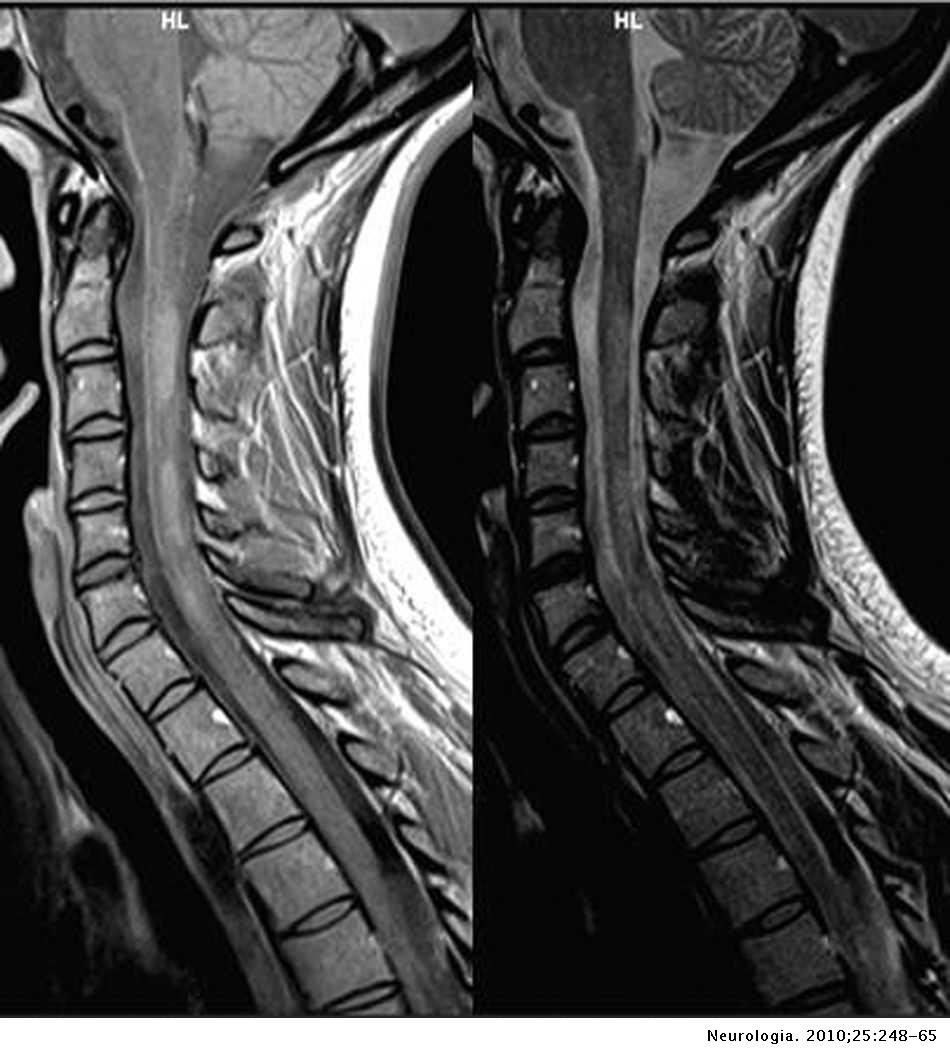

Lista muestra hermosas imágenes de resonancia magnética cerebral normal y anormal dinosenglish.edu.vn para que puedas explorar más en detalle.

Engineer Team : RESONANCIA MAGNETICA Magnetic Resonance Imaging – Clinical Images Hallazgos por resonancia magnética cerebral de nuestro paciente. M, 21 … Imágenes por resonancia magnética anormales como predictoras de mal … Imágenes por resonancia magnética anormales como predictoras de mal … Lesiones en resonancia magnética (RM) del encéfalo y la médula espinal … Pin en Resonancia Magnética del Encéfalo A) Resonancia magnética cerebral (RMC) mostrando infartos en … Caso 1: Edema cerebral visualizado mediante RM. (A) Secuencia T1 plano … Rascacielos dormir pasta tac y resonancia diferencias retrasar … Pin on Apuntes de Enfermería y T.C.A.E Resonancia magnética cerebral secuencia T2, que muestra lesión … Meningitis aguda en la enfermedad de Behçet | Reumatología Clínica Resonancia magnética coronal normal del cerebro Fotografía de stock – Alamy Imágenes de resonancia magnética, la imagen de la cabeza en diferentes … Resonancia magnética cerebral A) protocolo T1 sagital (Caso 1). Se … Resonancia magnética cerebral. Secuencia T1 corte sagital. Atrofia … Resonancia magnética de cerebro, cortes axiales, secuencias T2. Señal … Resonancia magnética de cráneo. A y B) Cortes axiales FLAIR … Resonancia magnética (RM) de cerebro, corte axial ponderado en T2: la … RM cerebral: Interpretación paso a paso | Kenhub Resonancia magnética de cerebro, cortes axiales, secuencias T2. Señal … De Resonancia Magnética De Cerebro Foto de archivo – Imagen de arteria … Top 107+ Imagenes de resonancia cerebral normal – Destinomexico.mx -Imagen por resonancia magnética del cerebro. a) Cortes sagital y axial … resonanCia magnétiCa Cerebral donde se observa hiperintensidad a nivel … MRI (Imagen de resonancia magnética) – Tomografía computarizada de la … Meningioma – NCI Imágenes por resonancia magnética coloreadas del cerebro sano del … Resonancia magnética cerebral en secuencia FLAIR, que muestra lesiones … Contraste resonancia magnetica cerebral – senturinthegreen Relación de los espacios de Virchow-Robin con la enfermedad de … Gliomatosis cerebral – Instituto Nacional del Cáncer Pin en Neurology. Recomendaciones para la utilización e interpretación de los estudios de … Fotografía De La Proyección De Imagen De Resonancia Magnética Del … atmósfera Dirigir Cumplir anatomia resonancia magnetica Desarrollar … Pin en #MEDICINA,#SALUD Resonancia magnética de la nasofaringe De Resonancia Magnética De Cerebro Foto de archivo – Imagen de polilla … Atrofia cortical global de predominio parietal en la Resonancia … Resonancia magnética cerebral | Download Scientific Diagram Neuroblog: Resonancia magnética cerebral en la trombosis crónica de … De Resonancia Magnética De Cerebro Imagen de archivo – Imagen de … ¿Cuáles son los riesgos de la resonancia magnética? – Integra Salud … Resonancia magnética cerebral al decimocuarto día de ingreso: área … Resonancia magnética. Corte axial mostrando área infartada en el … Resonancia magnética cerebral del paciente AV evidenciando lesiones en … -Ressonância magnética de encéfalo mostrando múltiplas imagens … Resonancia magnética cerebral secuencia FLAIR (Fluid Attenuated … Resonancia magnética cerebral con protocolo de epilepsia, en sección … Resonancia magnética cerebral en corte sagital. Se observa una evidente … Resonancia magnética craneal en la que se evidencian lesiones … Logran visualizar el cerebro a detalle más completo tras una resonancia … Así decide el cerebro la severidad de un castigo De Resonancia Magnética De Cerebro, Imagen de archivo – Imagen de … A) Resonancia magnética cerebral; Secuencia Tof: oclusión de arteria … Un estudio asocia la ansiedad con la aparición rápida del Alzheimer IMÁGENES DE 18 F-PR04.MZ PET FUSIONADA CON RESONANCIA MAGNÉTICA … Imágenes por resonancia magnética anormales como predictoras de mal … Tumores de la región pineal – Instituto Nacional del Cáncer Epilepsia: una historia de voces y fantasmas | Neurología Contribución de las imágenes de resonancia magnética por tensor de … Resonancia magnética secuencia T2 plano coronal de quiste epidermoide … Resonancia Magnética Cerebral del paciente: a. Aumento de… | Download … Resonancia magnética cerebral 2022 Síndrome de hemiconvulsión-hemiplejía-epilepsia. Seguimiento de un caso … Enfoque Radiologico: La resonancia magnética permite detectar lesiones … Resonancia magnética craneal T1 con contraste que muestra angiomatosis … guidewiz – Blog Resonancia magnética cerebral, secuencia SWI. Ribete hipointenso en la … resonAnCiA mAgnétiCA de ColumnA Con gAdolinio. Corte sAgitAl en t1 de … SEMANA 12: FUNDAMENTOS DE RESONANCIA MAGNÉTICA NUCLEAR. INDICACIONES Y … DIAGNÓSTICO DE ESCLEROSIS MÚLTIP Magnetic resonance imaging of the brain – Alchetron, the free social … Resonancia magnética de órbitas | Instituto Radiológico Dr. E Castillo Alteración de la marcha en un paciente post-trasplante hepático Resonancia magnética cerebral de un paciente sano (Ay B) y paciente que … Utilidad de la resonancia magnética craneal para el diagnóstico de la … Resonancia Magnética Del Cerebro El Tumor Cerebral Foto de stock y más … De Resonancia Magnética De Cerebro Imagen de archivo – Imagen de … ABDALLA RADIOLOGIA: NEURINOMA ACUSTICO Atrofia cortical global de predominio parietal en la Resonancia … Resonancia Magnética : Producción de la imagen MRI Brain Scan — Stock Photo © Bunyos30 #18724051 Mri (imagen de resonancia magnética) Monitor con imagen de captura de … Tomografía computarizada vs resonancia magnética: diferencia y … Tumores Cerebrales – Unidad de Neurocirugía RGS Resonancia magnética de la columna, sección sagital. Observe los discos … La resonancia magnética, una técnica imprescindible en el diagnóstico … Perfusión Cerebral por Resonancia Magnética | ¿Qué es? ¿Necesita Contraste? Resonancia Magnética Cerebro A: resonancia magnética, T2 coronal preoperatoria; se observa lesión en … Resonancia magnética cerebral — Foto de stock © Bunyos30 #27340623 La resonancia magnética se perfila como detector de mentiras | Futuro … Resonancia magnética cerebral en T1 con gadolinio, cortes axial (a … MRI brain : show brain tumor at right parietal lobe of cerebrum — Stock … NEUROIMÁGENES EN ENFERMEDAD DE PARKINSON: ROL DE LA RESONANCIA …